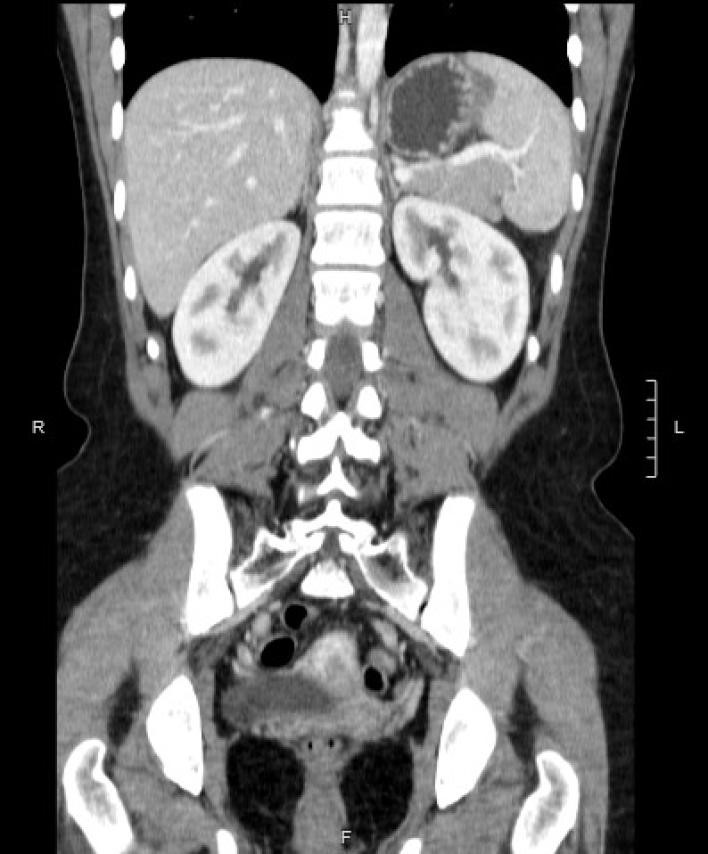

Se realizó tomografiía computarizada de control sin evidencia de lesiones residuales ni sitios isquémicos, constatado por la captación de contraste endovenoso en todo el volumen del órgano remanente (Figura 5 y Figura 6). La paciente se encontraba asintomática hasta el último control.

Figura 6: Tomografía computarizada de control. Corte coronal